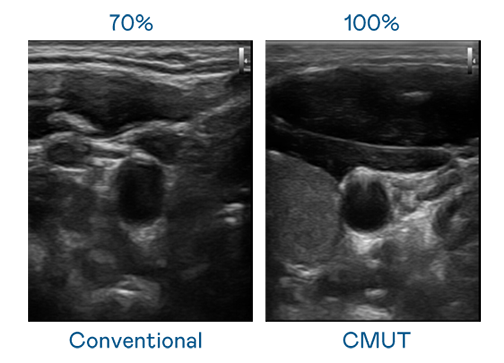

CMUT 技术是一种用电容式微机电元件来产生超音波讯号的技术。与传统 PZT 压电式技术相比,CMUT 频宽增加 30%,更宽频的超音波讯号让影像解析度大幅提升,是实现高影像品质医疗超音波扫描、促进精准医疗发展的关键技术。

超音波影像的解析度高低,首先取决于探头能发出的讯号频宽。3499拉斯维加斯 CMUT 可提供高清晰的超音波讯号,提供高频宽、高灵敏度、影像纹理细节更高的超音波影像,协助医护人员缩短影像判读时间及利用精准的医疗影像进行诊断。